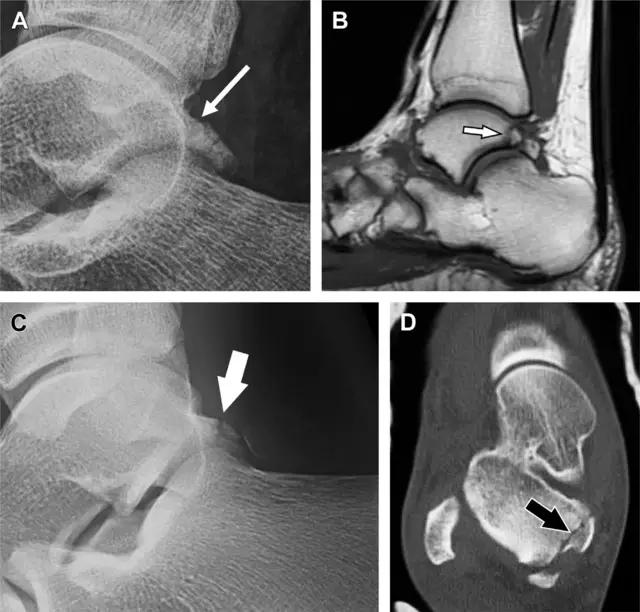

距骨后突有内侧结节和外侧结节,距骨后突内侧结节撕脱性骨折常发生在背屈内旋的*力暴**作用下。严重跖屈时,胫骨后缘和跟骨挤压距骨后突外侧结节呈楔形,易发生粉碎性骨折。这些骨折细微且需与三角骨鉴别。侧位片观察距骨后突骨折最佳,常规拍片很难发现,当高度怀疑这种骨折又没法做 CT 时,建议加做多个角度的外旋斜位片(图 5)。

图 5 距骨后突骨折。侧位片(A)和 MRI 矢状位 T1 加权像(B)均示后外侧突的简单骨折(箭头),再次阅片时才发现 X 线片上的骨折;侧位片(C)和 CT 横断面图像示后内侧突的粉碎型骨折(箭头)